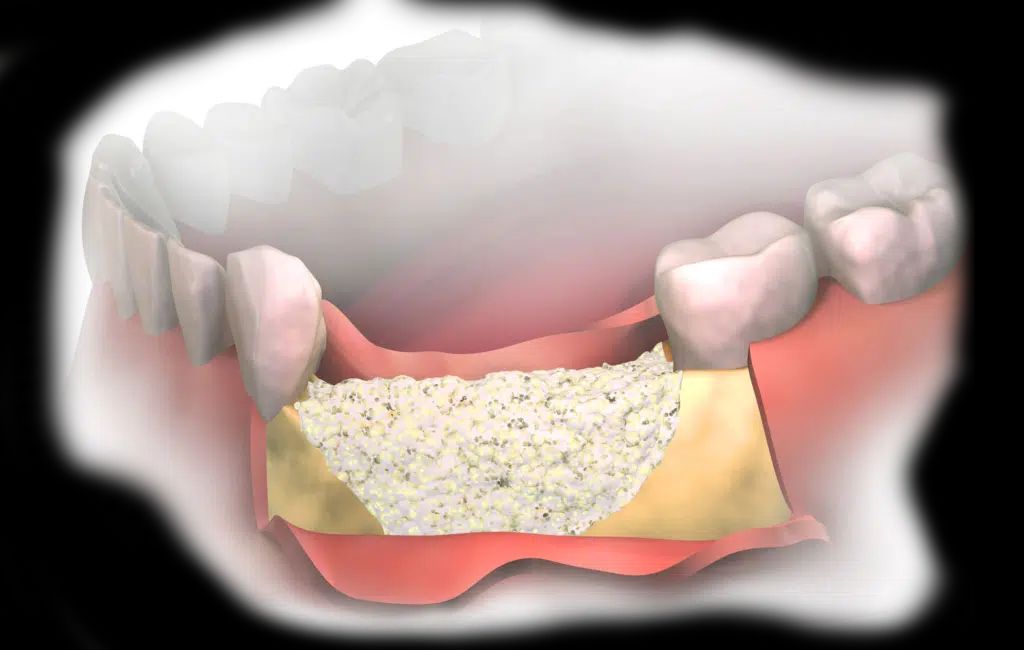

Rekonstrukcja i regeneracja tkanek za pomocą biomateriałów

Po utracie zęba, czy to w wyniku urazu, czy choroby, nierzadko konieczna jest odbudowa kości lub dziąsła. Korzystamy z najnowszych technologii, aby przywrócić Pacjentom pełną funkcjonalność i estetykę jamy ustnej.